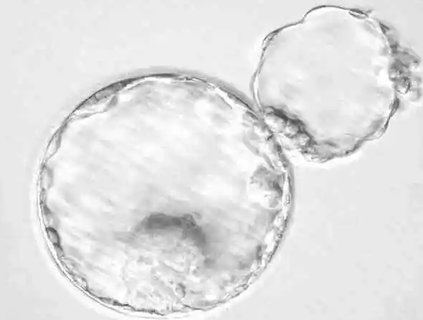

2024-08-02輔助孵化是輔助生殖技術中的一種微侵入性操作,旨在幫助胚胎更容易孵化并附著于子宮內膜。許多準備進行試管嬰兒的患者都關心這一技術是否能夠提高成功率。

2024-08-01在生育健康領域,卵泡的發育和成熟是懷孕過程中的關鍵環節。優勢卵泡是指在每個月經周期中發育最為成熟的卵泡,它含有最有可能成功受精和著床的卵子。